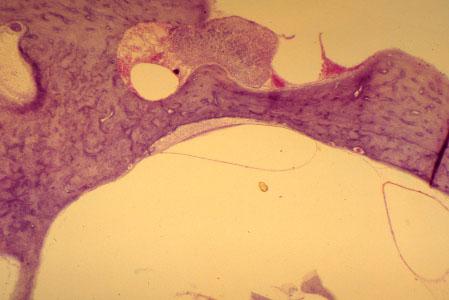

X-34 (4) Slide 84, Rodent Ear (H&E). Low power view of macula (mid-screen) adjacent to temporal bone.